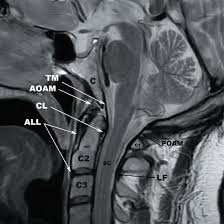

Medifyhome has collaborated with the best pathology laboratories that are NABL and NABH certified and follow ISO safety guidelines to provide the best MRI Screening CV Junction at an affordable price for needy individuals. Cervicothoracic Junction is a transitional area in the spine, which belongs to the cervical spine as well as Cervical spine. This area is crucial for protecting the spinal cord and nerves besides providing support to the head as well as helping in any movement. Because CV joints have a compound structure, it is vulnerable to diseases such as degenerative diseases, injuries by traumas, infections, or birth defects.

This imaging method creates additional value in the diagnostic imaging of various forms of disease such as nerve compression syndromes, spinal cord pathology, disc herniations, degenerative disc diseases, tumours etc. Screening using MRI provides healthcare givers with a clear view of bone and soft tissue around the cervicothoracic junction, diagnose the severity of the problem and advise on the appropriate line of action. To schedule an appointment for MRI Screening CV Junction, simply contact Medifyhome or call our customer care at +919100907036 or +919100907622 for more details and queries.